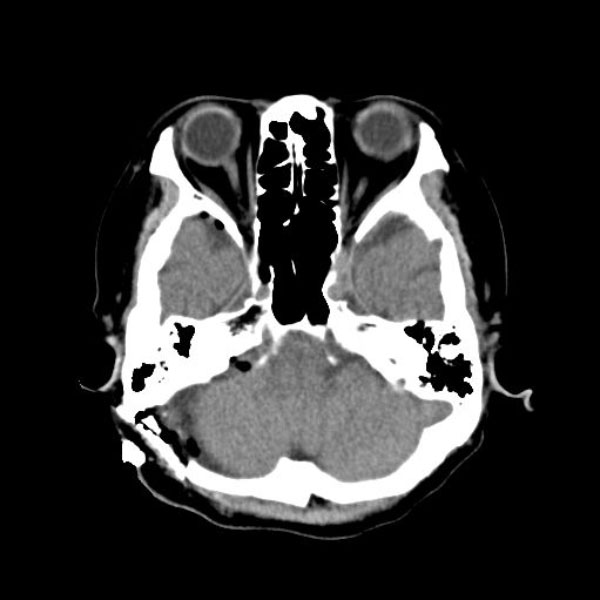

手術後

(CT)